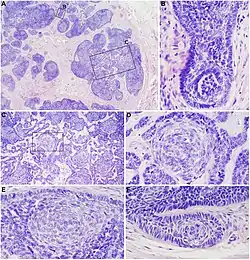

- Superficial basal-cell carcinoma, formerly referred to in-situ basal-cell carcinoma, is characterized by a superficial proliferation of neoplastic basal-cells. This tumor is generally responsive to topic chemotherapy, such as imiquimod, or fluorouracil, although surgical treatment is better able to ensure complete removal and confirm that there is not an underlying more aggressive subtype that was not sampled in the initial biopsy.

- Infiltrative basal-cell carcinoma, which also encompasses morpheaform and micronodular basal-cell cancer, is more difficult to treat with conservative methods, given its tendency to penetrate into deeper layers of the skin.

- Nodular basal-cell carcinoma includes most of the remaining categories of basal-cell cancer. It is not unusual to encounter heterogeneous morphologic features within the same tumor.

Nodular basal-cell carcinoma (also known as "classic basal-cell carcinoma") accounts for 50% of all BCC.[27] It most commonly occurs on the sun-exposed areas of the head and neck.[28]: 748 [29]: 646 Histopathology shows aggregates of basaloid cells with well-defined borders, showing a peripheral palisading of cells and one or more typical clefts.[27] Such clefts are caused by shrinkage of mucin during tissue fixation and staining.[30] Central necrosis with eosinophilic, granular features may be also present, as well as mucin. The heavy aggregates of mucin determine a cystic structure. Calcification may be also present, especially in long-standing lesions.[27] Mitotic activity is usually not so evident, but a high mitotic rate may be present in more aggressive lesions.[27] Adenoidal BCC can be classified as a variant of NBCC, characterized by basaloid cells with a reticulated configuration extending into the dermis.[27]

There are mainly three patterns of aggressiveness, based mainly the cohesion of cancer cells:[33]

| Low-level aggressive pattern | Moderately aggressive pattern | Highly aggressive pattern |

|---|---|---|

|

|

|